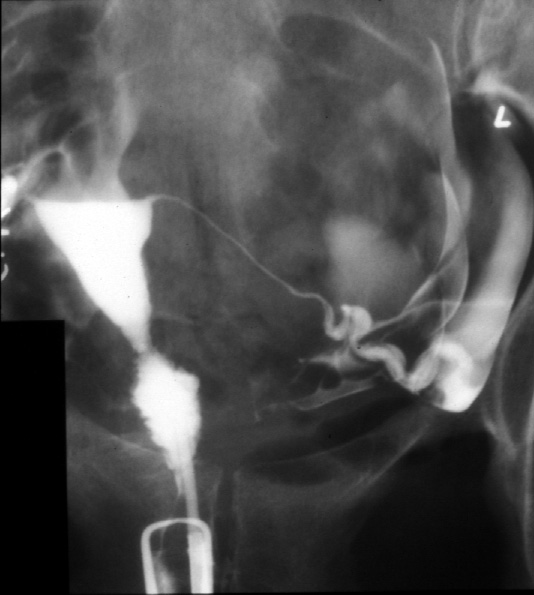

Note. The cervical canal cannulated and contrast is injected.

Identify -- cervical canal, internal cervical os, uterine cavity, isthums

of uterine tube, ampulla of uterine tube